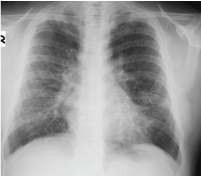

A 55-year-old male patient; was sent to the chest diseases clinic because of abnormal chest X-ray findings during preparation for cholecystectomy operation. The patient had no active respiratory complaints. He had no other special feature other than 50 pack/year smoking in his medical history. Blood pressure: 130/75 mmHg, pulse rate: 73/min and rhythmical, respiratory rate: 15/min, SpO2: 97% and no pathological findings in the respiratory system. He had bilateral radiopacity which was more pronounced in the upper zones in chest X-ray. In thorax computed tomography (CT), there were peripherally located consolidations and occasional glass ground appearances. These abnormalities were more prominent in the upper lobes rather than lower lobes. Respiratory function test results; forced vital capacity (FVC): 2.63 L (70.8%), forced expiratory volume in 1 second (FEV1) 2.19 L (71.3%), FEV1/FVC 82.68, and diffusing capacity of the lungs for carbon monoxide (DLCO) 75%.

Figure 1: Image from chest X-ray. View Figure 1

Chest X-ray is often normal in amyloidosis. Bilateral, peripheral, subpleural nature, lower zone dominance and sizes between 0.5 cm and 15 cm in diameter are the general features of amyloidosis-related parenchymal nodules [1,3]. These features are valid for our case too except upper zone dominance. It is often diagnosed incidentally. It is important to diagnose these parenchymal nodules, as these can be related with an infection, a neoplasm or vasculitis [1-5]. Metastatic pulmonary calcifications can also be seen due to chronic renal failure if it is secondary to renal failure [2]. Calcifications due to renal failure are mostly seen in the upper lobes and central.